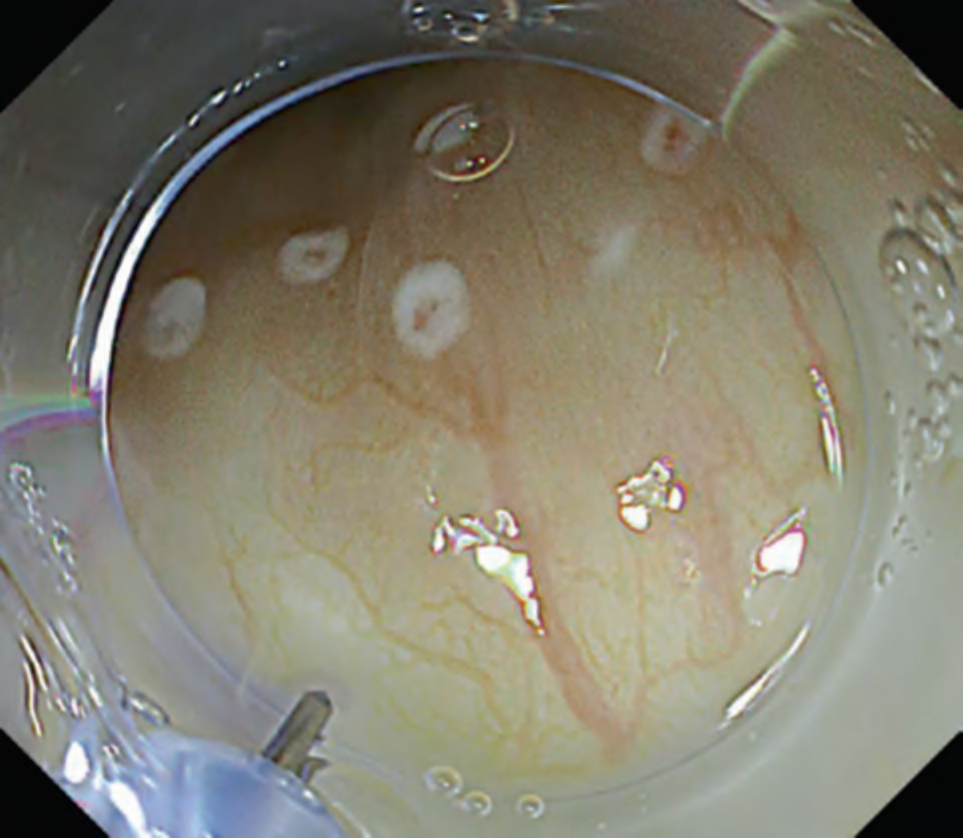

In this mode, deep blood vessels are displayed in green and superficial blood vessels in red. Images obtained by this mode are similar to those by narrowband imaging; however, bile in the digestive tract lumen does not turn red, facilitating mucosal observation in colonoscopy with poor preparation. It is also reported that this mode enables to visualize subtle inflammatory activity that is unable to find in white light imaging in patients with ulcerative colitis (. Fig. 8) [9].

Fig. 8 White light imaging versus RDI mode 3 in cases with ulcerative colitis. a White light imaging of case with Mayo score 0. b RDI mode 3 of case with Mayo score 0. c White light imaging of case with Mayo score 1. d RDI mode 3 of case with Mayo score 1. e White light imaging of case with Mayo score 2. f RDI mode 3 of case with Mayo score 2.